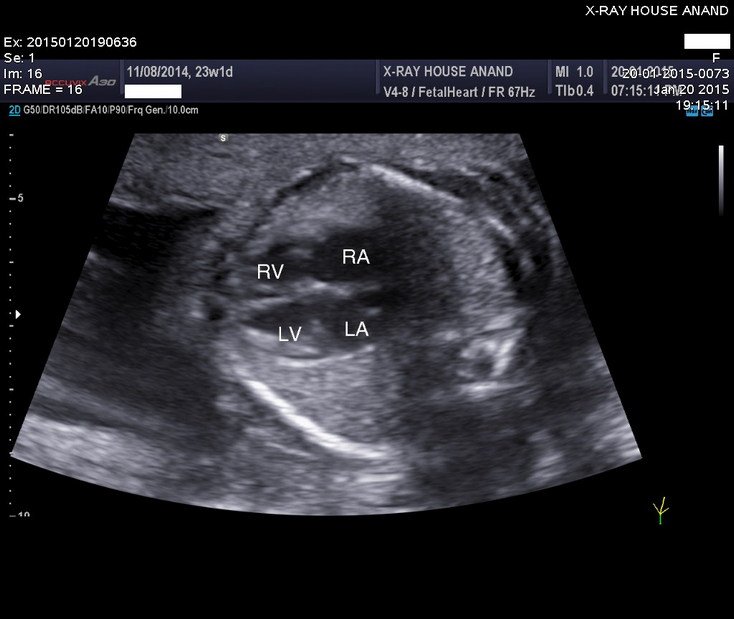

2D Sonography-Foetal Heart